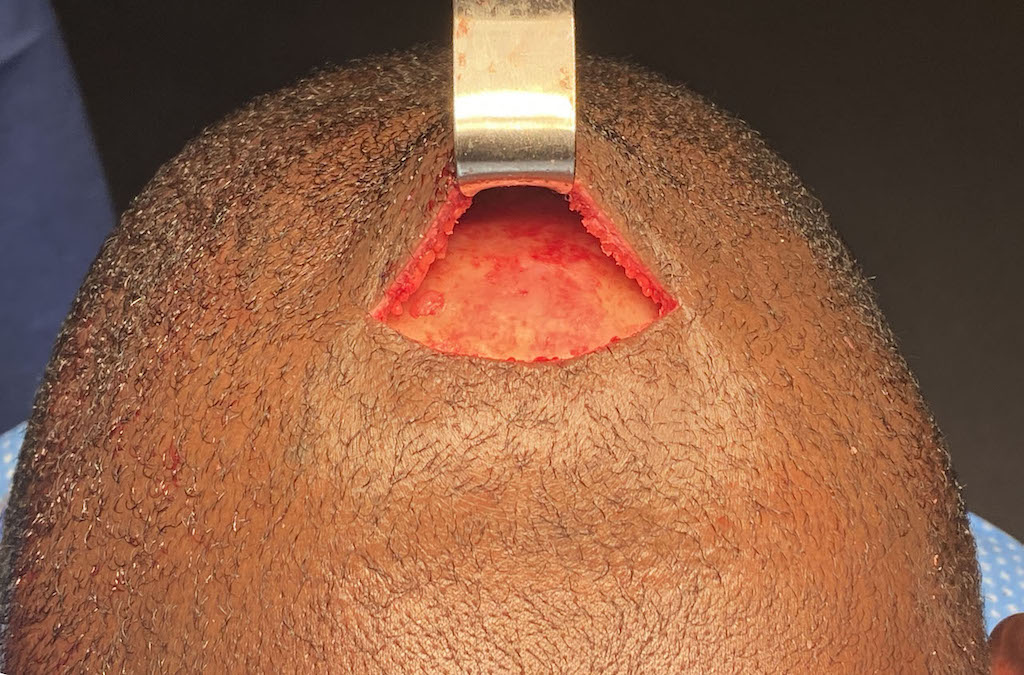

Desire for reduction of prominent occipital knob deformity.

Intraoperative result from occipital knob skull reduction through a direct small scalp incision.

Desire for reduction of prominent occipital knob deformity.

Intraoperative result from occipital knob skull reduction through a direct small scalp incision.